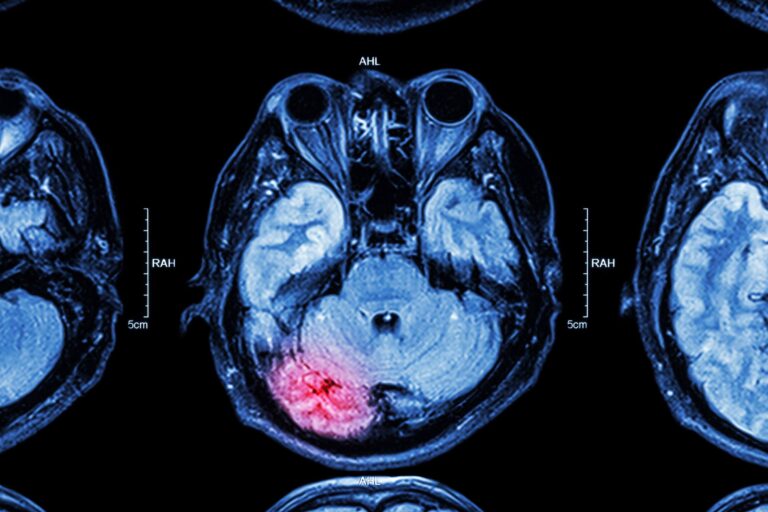

DTI (Diffusion Tensor Imaging) is an advanced type of MRI brain scan that maps the brain’s white matter pathways with remarkable precision. Unlike standard MRI scans that show brain structure, DTI tracks water movement along nerve fibers to reveal the integrity and organization of white matter tracts—the neural highways connecting different brain regions.

• Detects brain damage invisible on standard MRI

DTI scans diagnose and evaluate a wide range of neurological conditions by revealing white matter pathway integrity, brain connectivity, and neural damage invisible on standard MRI.

DTI can detect abnormalities months or years before conventional MRI shows changes.